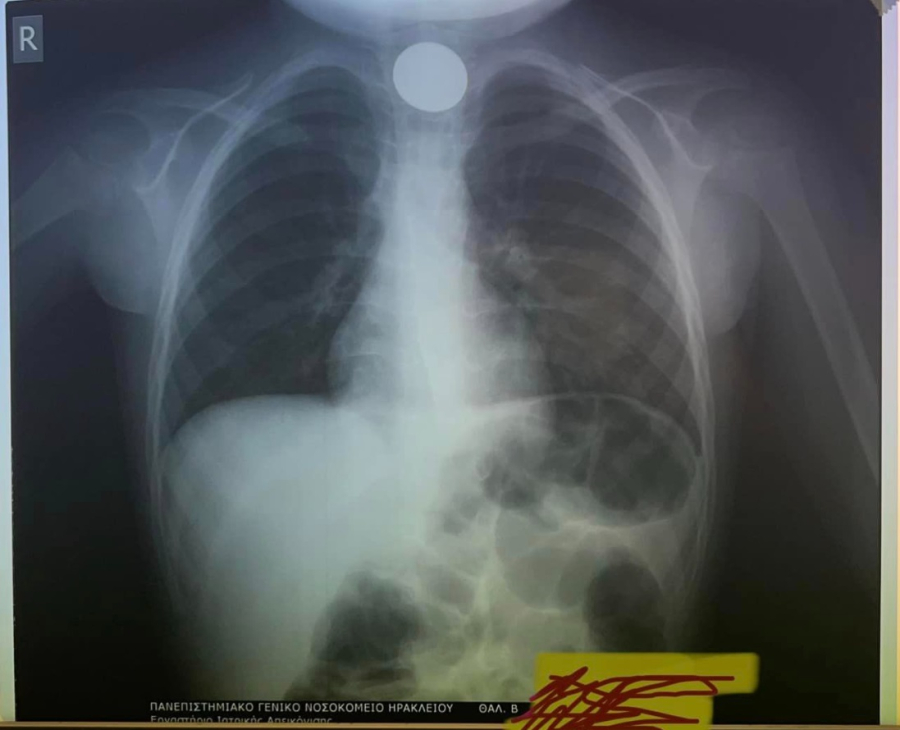

Όταν έφτασαν στο ΠΑΓΝΗ, η πρώτη κίνηση των γιατρών ήταν να του κάνουν ακτινογραφία, για να δουν σε ποιο σημείο ακριβώς είχε σταθεί το νόμισμα και μετά προχώρησαν στη διαδικασία αφαίρεσής του.